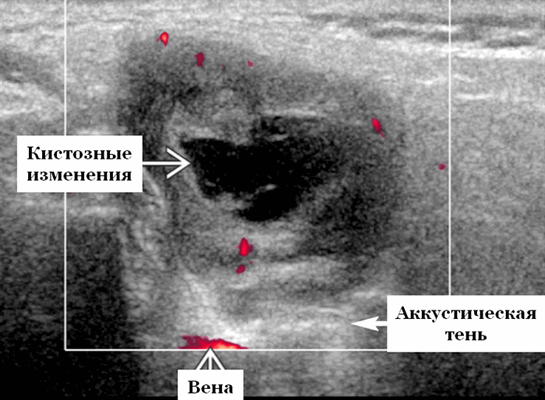

Важнейшее место в дифференциальной диагностике различных внеорганных опухолей шеи занимает ультразвуковое исследование. В В-режиме метастазы в лимфатические узлы имеют неоднородную структуру, капсулу толщиной до 2 мм, невриномы — изоэхогенную однородную структуру без выраженной капсулы, кисты - гипоэхогенную структуру с наличием мелкодисперсного жидкого содержимого и капсулу толщиной до 1.5 мм. Кровоток по сонным артериям характеризуется отсутствием локального повышения скорости, что свидетельствует о неизменности гемодинамики. В 30 % случаев определяют гемодинамически значимую компрессию яремной вены. Сосудистый рисунок неврином чаще представлен множеством сосудов, преимущественно артериями, диаметром до 2.2 мм с коллатеральным типом кровотока, в шванноме сосуды с венозным характером кровотока, внутри кист сосудистый рисунок не выражен.

Серошкалльное УЗИ. Четко выраженная опухоль от округлой до овальной формы. Гипоэхогенная по отношению к фоновой паренхиме околоушной железы. Часто присутствуют анэхогенные кистозные компоненты. Заднее акустическое усиление или через передачу часто присутствует даже в преимущественно солидных опухолях. Сужающиеся концы на границе раздела опухоль-нерв обычно не наблюдается, так как лицевой нерв обычно слишком мал, чтобы быть визуализированным на ультразвуковом сканировании, но если присутствует, настоятельно рекомендуется выставлять диагноз шванномы. Отсутствие сопутствующей шейной лимфаденопатии

Цветной допплер. От легкой до умеренной степени внутренней гиперваскуляризации (кротокок компрессируется давлением датчика).